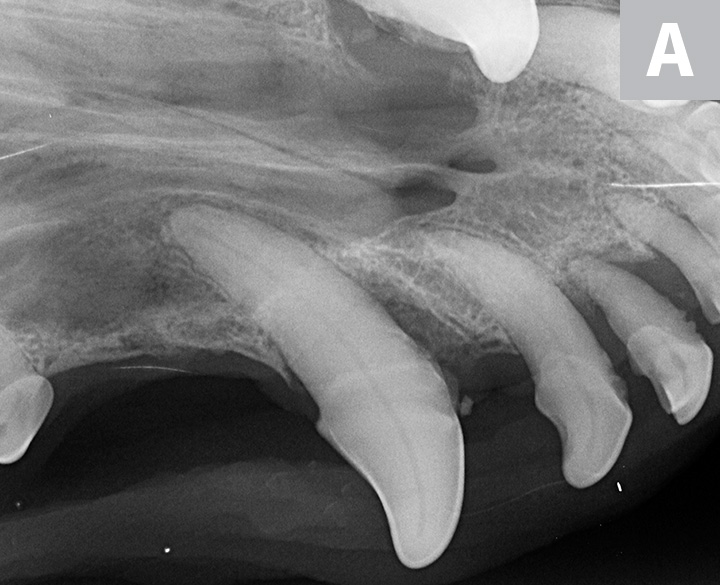

Three dental radiographs.

Figure 2

Dental radiographs of the right (A) and left (B) maxillary canine teeth (lateral views) and the rostral maxillae (C; occlusal view) confirmed mild horizontal and severe vertical bone loss at the mesial aspect of both maxillary canine teeth. Moderate to severe horizontal bone loss at the right maxillary first incisor tooth (blue arrow) and total loss of attachment with inflammatory root resorption at the right maxillary second incisor tooth (yellow arrow) were present. The remaining maxillary incisor teeth were affected by mild horizontal bone loss. Although the occlusal view of the rostral maxillae is slightly asymmetric, osteolysis was evident in the area of the left palatine fissure (red arrow). Mild horizontal bone loss was diagnosed at several other teeth. In addition, retained root tip of the left maxillary (presumably) first premolar tooth (white arrow) was identified.